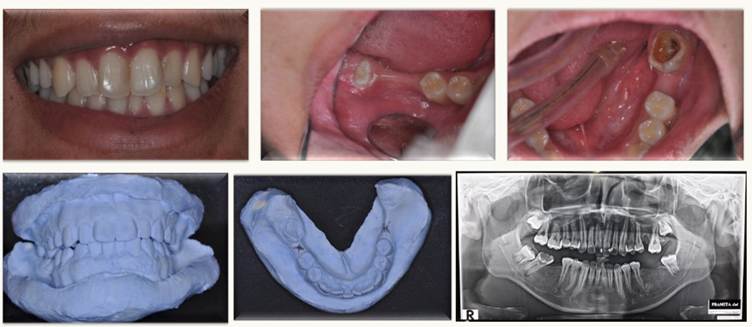

Pada sesi klinis, peserta diajak menelaah tiga kasus nyata, meliputi:

- Penempatan single implant pada resorpsi alveolar ringan,

- Multiple implant pada resorpsi tulang lanjut,

- Ridge splitting technique untuk augmentasi horizontal dan immediate implant placement.

Melalui dokumentasi before-after, Prof. Ruslin memberikan penjelasan strategis terkait perencanaan kasus, teknik pembedahan, hingga evaluasi pasca perawatan. Peserta memperoleh gambaran aplikatif tentang bagaimana teknologi terbaru dapat mendukung penanganan kasus kompleks.